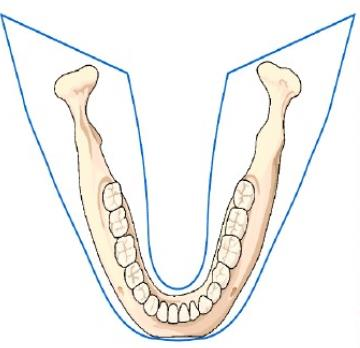

全景机即“曲面体层X线机”,利用曲面体层摄影技术通过一次曝光对全口牙齿、牙周组织及相邻解剖结构进行全面二维成像,显示范围包含整个口腔,就像是一张“牙齿大合照”。

▲全景机成像范围

全景片常用于口腔疾病的大范围筛查,例如全口牙齿缺失筛查、颌骨多发病变、颌骨外伤、颌骨发育畸形及牙齿、牙周疾患的诊断。得益于其广泛的成像视野,全景机在正畸领域也能起到数据辅助的作用。